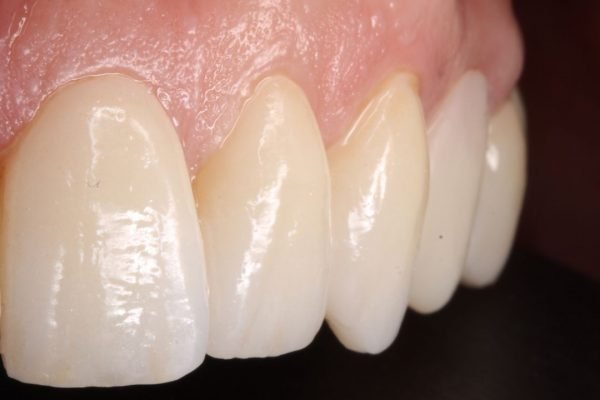

En la actualidad, la tecnología en odontología ha permitido realizar estos tratamientos de manera más eficiente y cómoda para el paciente. La técnica del Clon digital o Paciente Virtual, por ejemplo, permite obtener un modelo digital dinámico del paciente, lo que permite diseñar todo el tratamiento digitalmente y utilizar bibliotecas de dientes naturales para obtener un resultado estético y funcionalmente óptimo. Gracias a esta técnica, se pueden realizar tratamientos en menos citas y con mayor comodidad para el paciente.

En nuestra clínica dental, ofrecemos una atención personalizada y de alta calidad, y nos enfocamos en un enfoque multidisciplinar para la rehabilitación dental bimaxilar. Trabajamos en conjunto con especialistas en ortodoncia, periodoncia y endodoncia para garantizar el mejor resultado posible en cada tratamiento personalizado. Además, ofrecemos diferentes tratamientos personalizados según las necesidades de cada paciente, como carillas dentales, implantes y ortodoncia, todo esto con la finalidad de ayudarte a recuperar tu sonrisa y mejorar tu salud dental.